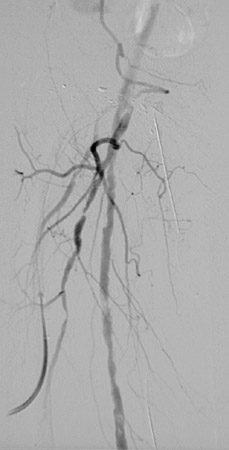

The angiogram views above and below reveal multiple areas of atherosclerotic narrowing involving branches of the right femoral artery.